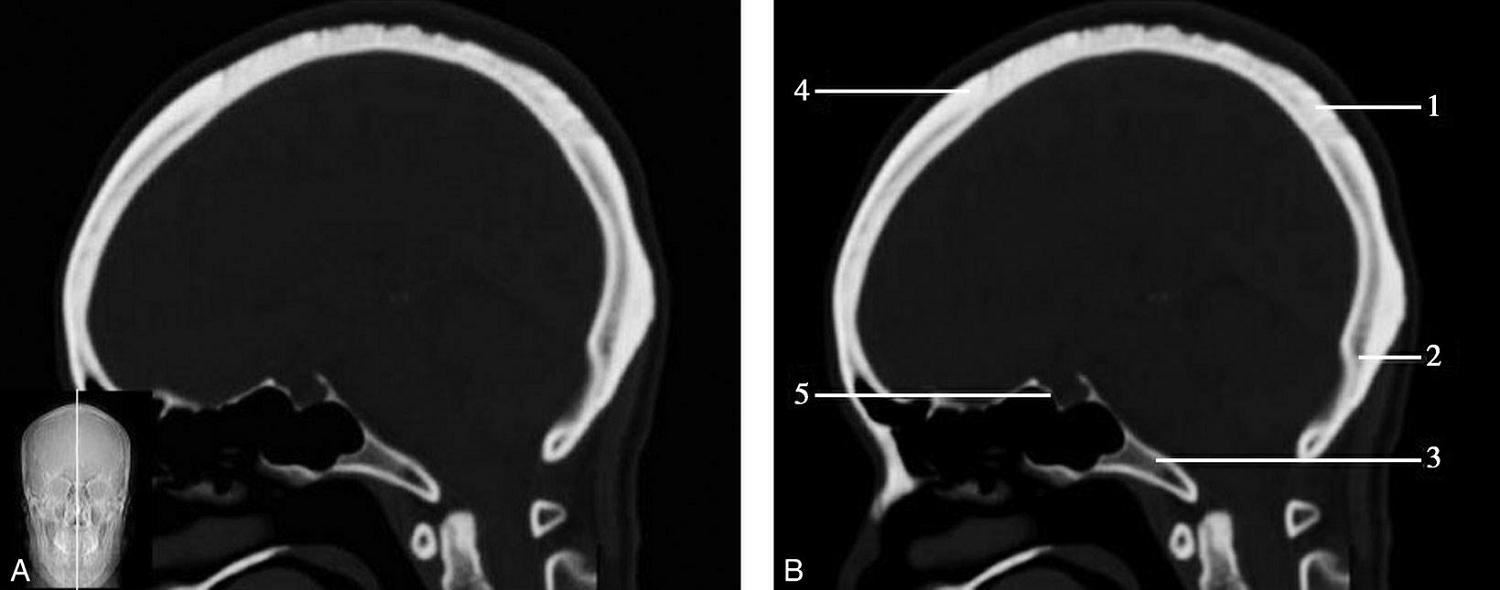

图1-2-60 正中矢状面骨窗CT

A.矢状面;B.矢状面标注

1.顶骨;2.枕骨;3.斜坡;4.额骨;5.蝶鞍